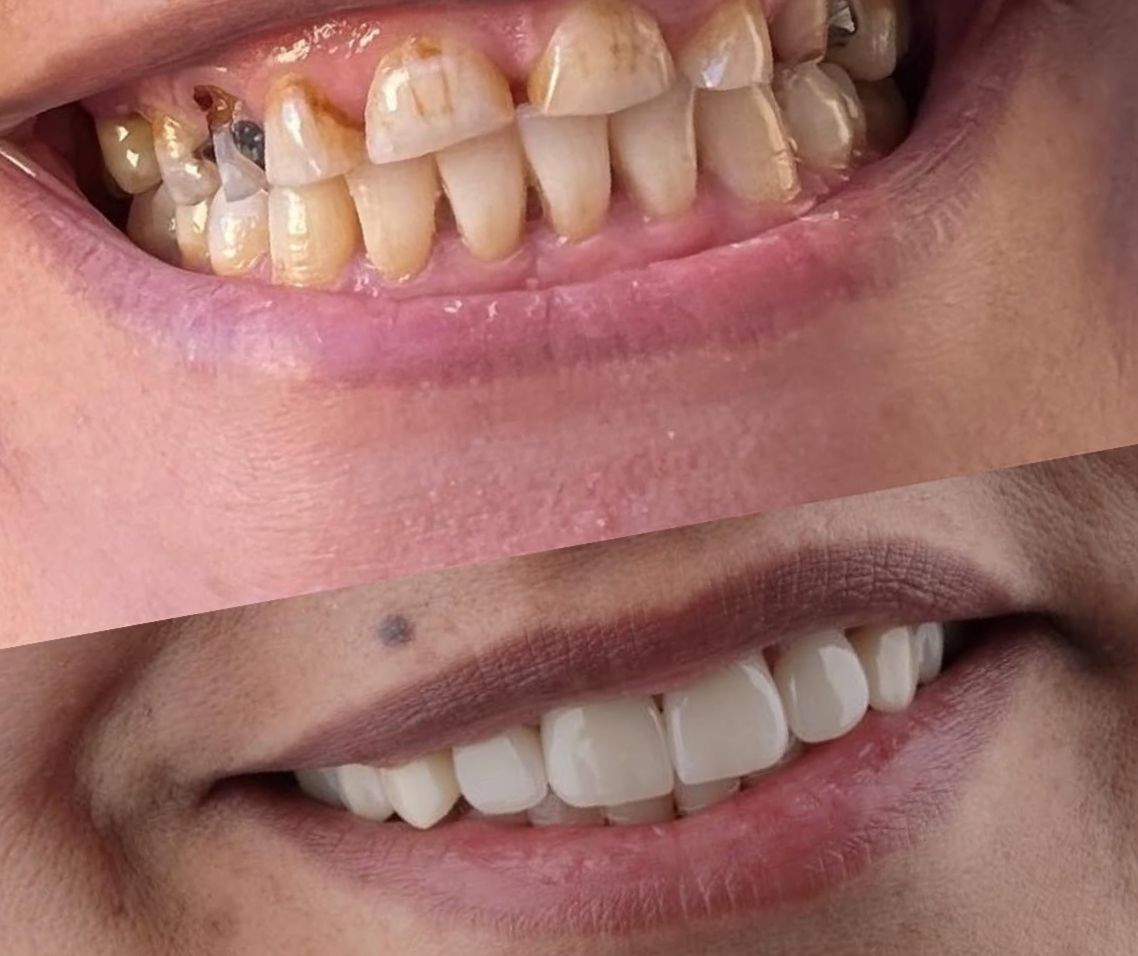

Dental Treatment Before and AfterClick To Enlarge White Teeth Lips Closeup Teeth Whitening Before After Teeth Whitening Transformation Before After Teeth Transformation Before After Man White Teeth Mustache Smile Teeth Whitening Transformation Before After Teeth Before After Transformation Teeth Before After Treatment Teeth Before After Composite Bonding Teeth Whitening Transformation Before After dental treatment dental treatment dental treatment dental treatment dental treatment dental treatment dental treatment dental treatment dental treatment dental treatment dental treatment dental treatment dental treatment dental treatment dental treatment dental treatment dental treatment dental treatment dental treatment